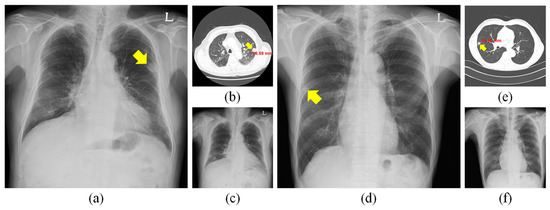

| LES+ Abnormal | A consensus of 2/3 is required to confirm the presence of one or more pulmonary lesions. In addition, CXR may contain other pathological abnormalities. A consensus of 2/3 is required to confirm these. |

| LES− Abnormal | A consensus of 3/3 is required to confirm the absence of any pulmonary lesions. In addition, CXR contained other pathological abnormalities. A consensus of 2/3 is required to confirm these. |

| Normal | A consensus of 3/3 is required to confirm the CXR did not show any pathological abnormalities. |